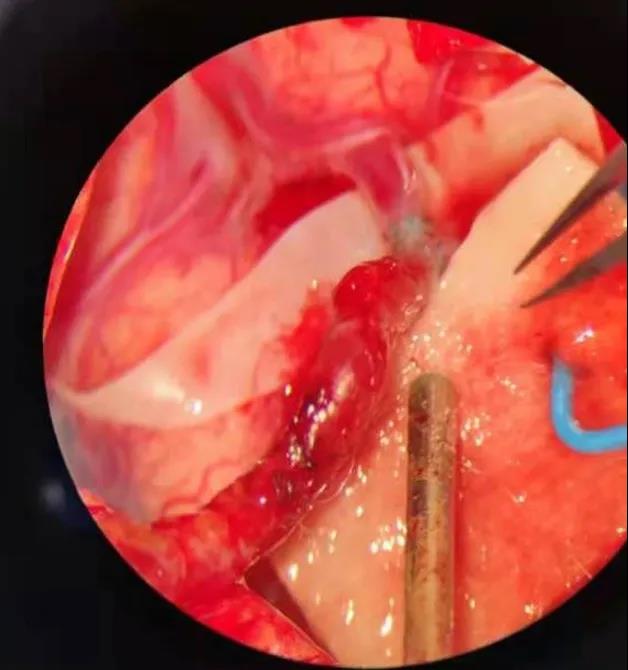

“经过术前造影,我们找到一根管径与颅外颈动脉匹配的大脑中动脉的分支血管作为受体血管,这相当于在颅内进行‘南水北调’”。吴主任慎重考虑,为确保手术风险降到最低,他在科内召开手术讨论,为患者量身制订手术方案,同时脑血管搭桥术因难度极高,风险极大,不仅需要精湛的显微外科技术、高超的血管吻合技术,还需要配套高精尖设备做支撑。

一体化复合手术室,吴卫江和神经外科介入医生刘晓勇共同配合,打开一个仅有4厘米的骨窗,找到与颅外血管匹配的健康血管,通过造影定位血流供应区域,借助显微镜,吴主任开始端侧吻合,在1.5毫米的吻合口处缝了15针,两根血管成功相接,血流状况良好。

“这就像是在头发丝上跳舞”,吴卫江打趣道:“现在我们等于给大脑重建了一条高速公路,绕过塌方的公路,连接两头”。手术顺利完成,患者立即转入到神经外科监护室进行围手术期的进一步监护治疗。

通过神经外科医疗和护理团队的精心治疗,患者恢复很快。术后复查脑血管造影颅内吻合口很通畅,MRI检查也提示大脑的侧支循环明显增加、脑血供明显改善。